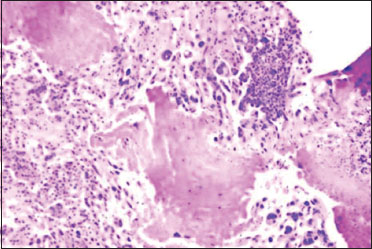

A 19-year-old female presented with the chief complaints of recurrent and painless gross hematuria for the past 6 months with a single acute episode of gross hematuria and pain in the hypogastrium before her admission to the gynecological outpatient department. Her medical history revealed that she had been taking treatment from a private center and was on and off on antibiotics throughout this period owing to her clinical findings, although most of her culture reports were sterile. Her past as well as her family history of any cancer was non-contributory. On general physical examination, she was thin built and anemic. Per abdomen examination revealed mild tenderness in the hypogastrium with no evidence of ascites or any organomegaly. She had attained menarche at the age of 13 years and had regular cycles with an average flow. Her gynecological examination was unremarkable. Her subsequent ultrasound pelvis showed a nongravid everted uterus and unremarkable adnexa. On per rectal examination, the rectal mucosa was free. All other systemic examinations were within the normal limits. Her routine hematological investigations revealed microcytic hypochromic blood picture. Urine and blood cultures were negative. Kidney and liver function tests were normal. Serum antibodies to human immunodeficiency virus, hepatitis B surface antigen, and syphilis were negative. X-ray chest was normal. To investigate the cause of hematuria, cystoscopy was planned, which revealed hemorrhagic, polypoidal masses located at the roof of the urinary bladder with extension toward the vaginal vault. During the cystoscopy, a diagnostic biopsy was taken and was sent for histopathological examination. Microscopic sections showed a deep infiltrative tumor showing sheets of trimorphic cells which appeared highly bizarre exhibiting plexiform pattern with numerous giant cells. Sections, in addition, showed marked central hemorrhage and striking atypia with numerous mitotic figures [Figure 1]. On the basis of these findings, a differential diagnosis of extragonadal mixed germ cell tumor with a predominant choriocarcinomatous component, undifferentiated transitional cell carcinoma, and malignant mesenchymal tumor (sarcoma) of the urinary bladder was made.

| Figure 1:Microphotography exhibiting trophoblastic neoplasia with areas of necrosis (H and E; ×200)